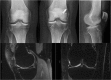

Recent findings: There has been interesting new research related to ACL reconstruction. As understanding of knee biomechanics following ACL injury and reconstruction has changed over time, many surgeons have changed their surgical techniques to low anterior drilling to position their femoral tunnel in an attempt to place the ACL in a more anatomic position. Even with this change in the femoral tunnel position, 85% of knees following ACL reconstruction have abnormal tibial motion compared to contralateral non-injured knees. Studies have shown increases in inflammatory cytokines in the knee following ACL injury, and newer MRI sequences have allowed for earlier objective detection of degenerative changes to cartilage following injury. Recent studies have shown that injecting IL-1 receptor antagonist and corticosteroids can modulate the post-injury inflammatory cascade. ACL reconstruction does not prevent the development of OA but can improve knee kinematics and reduce secondary injury to the cartilage and meniscus. Advancements in imaging studies has allowed for earlier detection of degenerative changes in the knee, which has allowed researchers to study how new interventions can alter the course of degenerative change in the knee following ACL injury.

Figures